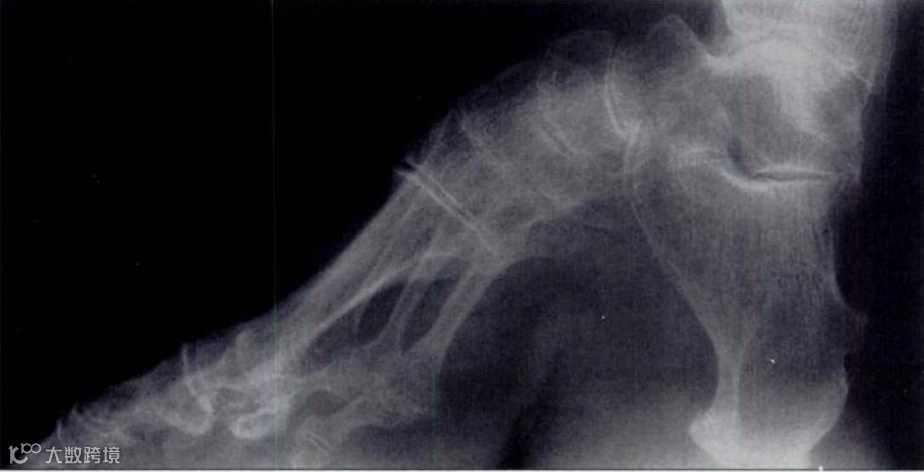

缠足是中国古代社会对女性身体的极端规训,不仅是一种文化现象,更是一种深刻的身体暴力。今天我们通过X线图像来窥探和审视这一古老习俗的残酷性,无声见证历史伤痕,隔空感受古代女性在成长过程中所承受的痛苦与压抑。

缠足的X线片显示外侧脚趾扭曲和足弓明显畸形。

(此图来源于香港医学科学博物馆,由香港放射科医生学院1996年捐赠)

X线影像让我们清晰地看到 “三寸金莲” 背后隐藏的残酷真相:足部骨骼的畸形、关节的退行性变以及足弓的彻底破坏、畸形,无一不是缠足这一习俗对女性身体造成的永久性伤害。这些影像不仅是医学的证据,更是历史的无声见证,提醒我们那段女性被迫承受痛苦与压抑的岁月。